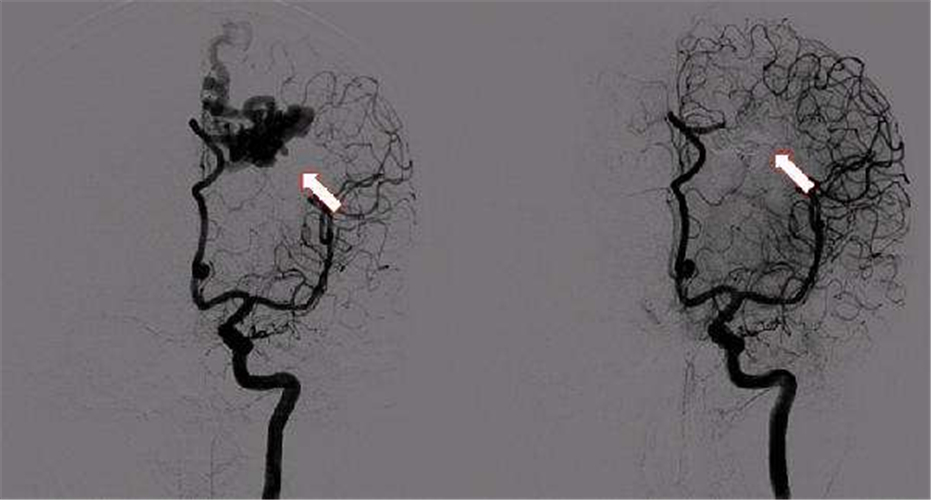

腦供血不足血管造影